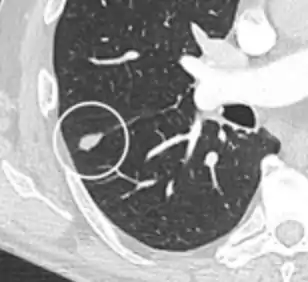

A "notch sign".[9]

- Margin morphology: a spiculated margin is a risk factor for cancer.[8] Benign causes tend to have a well defined border, whereas lobulated lesions or those with an irregular margin extending into the neighbouring tissue tend to be malignant.[10] In particular, spiculations are highly predictive of malignancy with a positive predictive value up to 90%.[9] Also, a "notch sign", which is an abrupt indentation of the nodule, increases the risk of cancer, but may also be found in granulomatous diseases.[9]